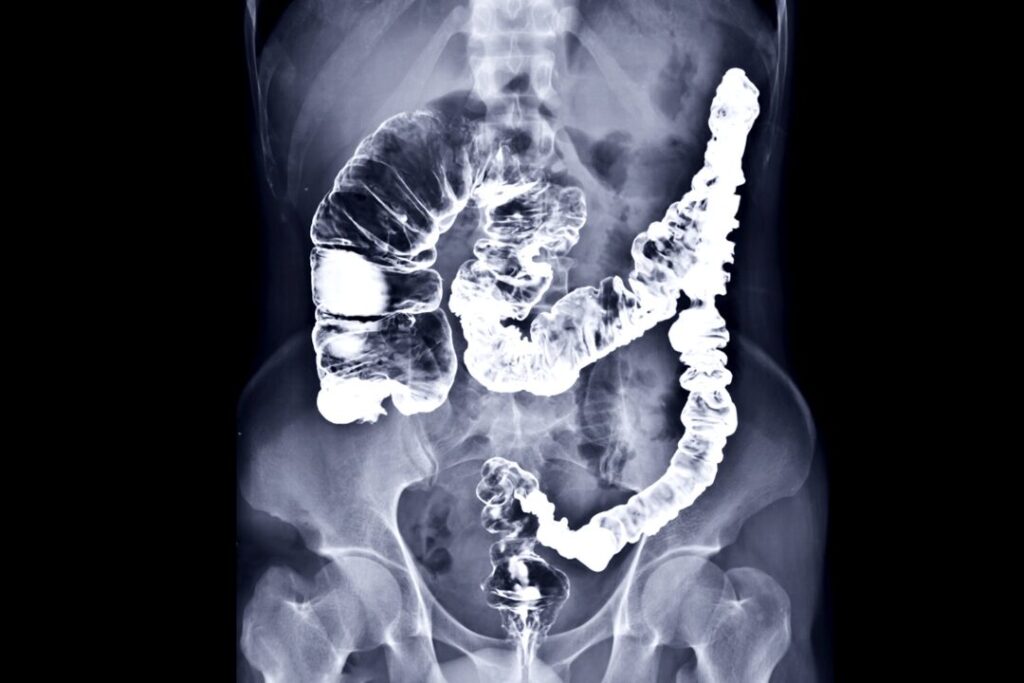

El cáncer de colon es uno de los cánceres más comunes, especialmente entre hombres mayores de 50 años, y afecta de manera desproporcionada a la población latina en los EE.UU. Este tipo de cáncer ocurre cuando se desarrollan pólipos en el revestimiento del colon, que con el tiempo pueden volverse cancerosos si no se detectan a tiempo. Según estudios, el cáncer de colon es la segunda causa principal de muerte relacionada con el cáncer en EE.UU.

- Chequeos regulares: A partir de los 45 años (o antes si hay antecedentes familiares), es fundamental realizar colonoscopías periódicas para detectar posibles pólipos a tiempo.